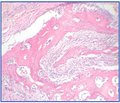

Яковленко В.В.(1), Сокрут В.Н.(1), Синяченко О.В.(1), Егудина Е.Д.(2)

(1) — Донецкий национальный медицинский университет имени Максима Горького, г. Красный Лиман

(2) — Днепропетровская государственная медицинская академия

Журнал «Травма» Том 16, №4, 2015

Рубрики:

Травматология и ортопедия

Разделы: